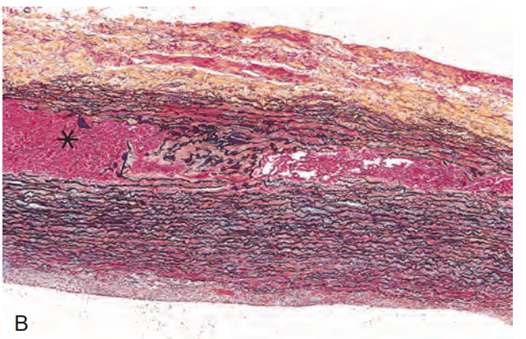

Vad ser du på bilden?

Aortadissektion

Falsk lumen på denna bild